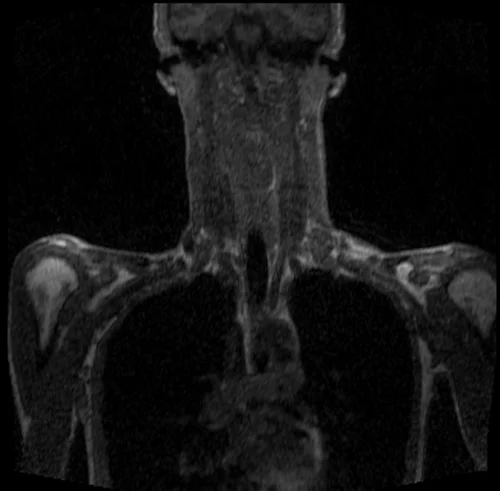

MRA subclavian artery coronal T1 3D FLASH images